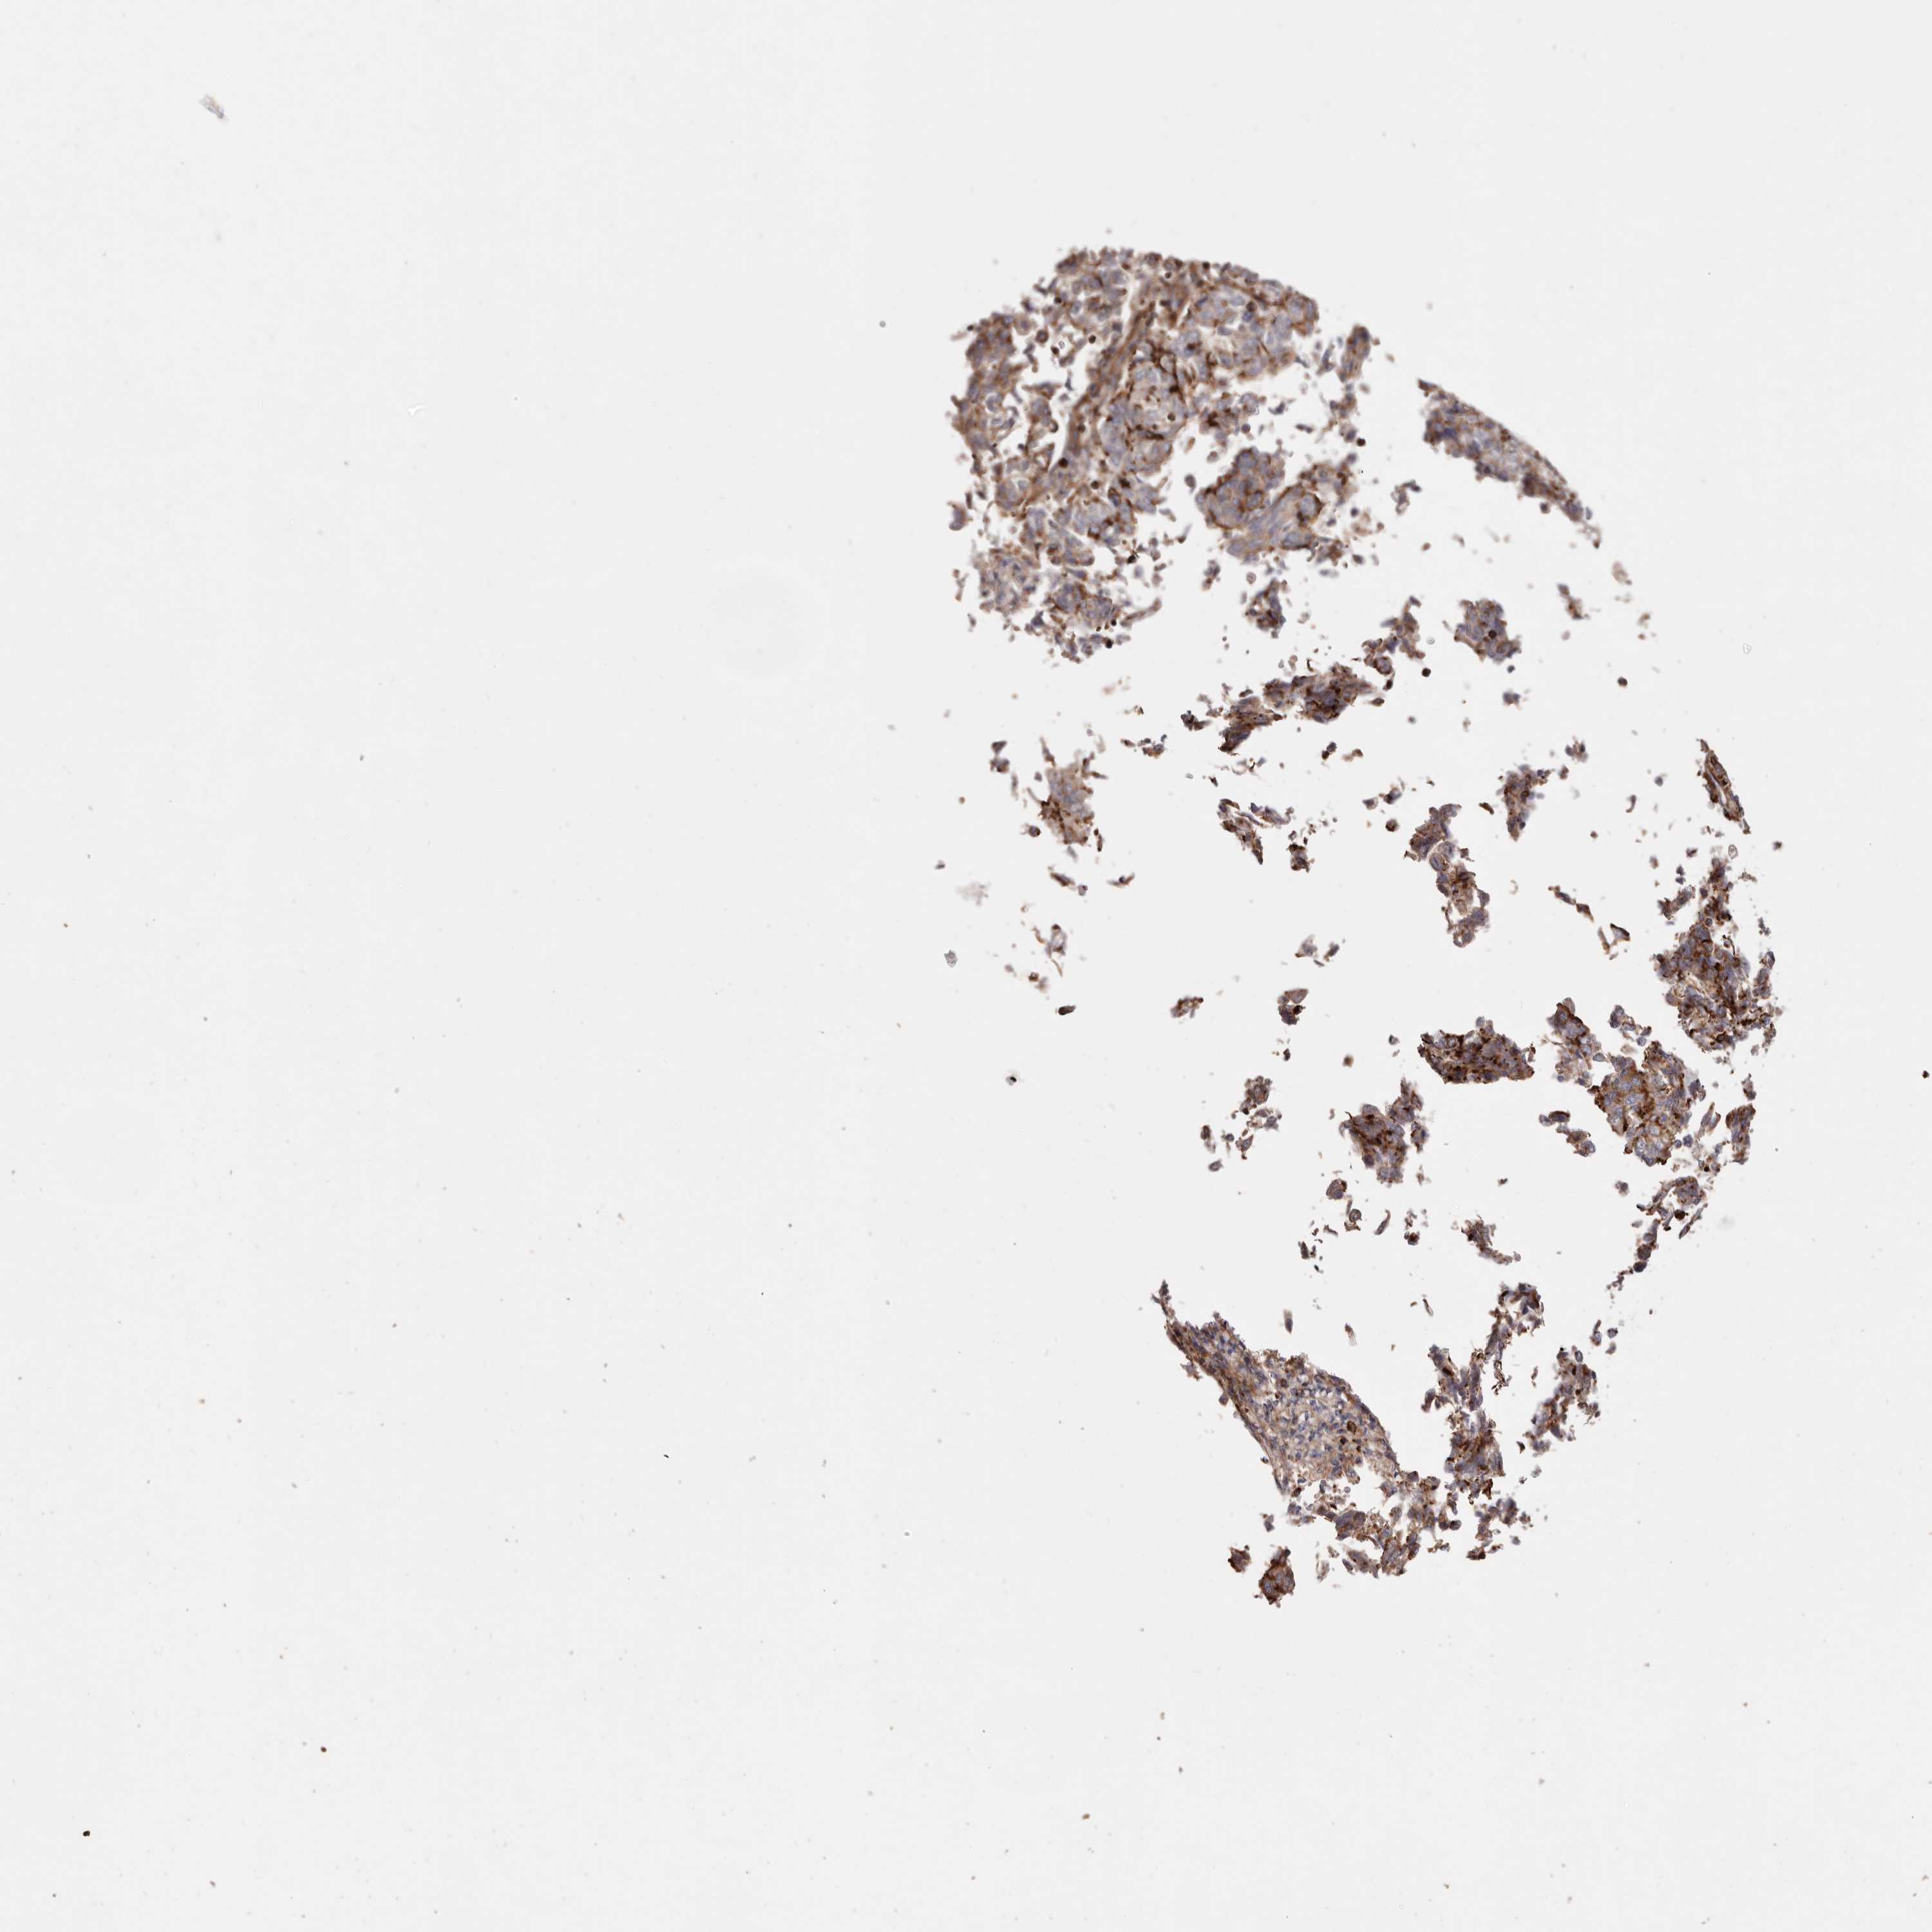

ENDOMETRIAL CANCER - Protein expressioni

A mouse-over function shows sample information and annotation data. Click on an image to view it in a full screen mode. Samples can be filtered based on level of antibody staining by selecting one or several of the following categories: high, medium, low and not detected. The assay and annotation is described here.

Note that samples used for immunohistochemistry by the Human Protein Atlas do not correspond to samples in the TCGA dataset.

Antibody stainingi

Antibody staining in the annotated cell types in the current human tissue is reported as not detected, low, medium, or high, based on conventional immunohistochemistry profiling in selected tissues. This score is based on the combination of the staining intensity and fraction of stained cells.

Each image is clickable and will lead to virtual microscopy that enables deeper exploration of all samples and also displays staining intensity scores, fraction scores and subcellular localization as well as patient and tissue information for each sample.

Antibody HPA004912

Antibody HPA013350

Antibody CAB012209

Staining

High

Medium

Low

Not detected

Intensity

Strong

Moderate

Weak

Negative

Quantity

>75%

75%-25%

<25%

None

Location

Nuclear

Cytoplasmic/membranous

Cytoplasmic/membranous,nuclear

Adenocarcinoma, NOS

Adenocarcinoma, metastatic, NOS